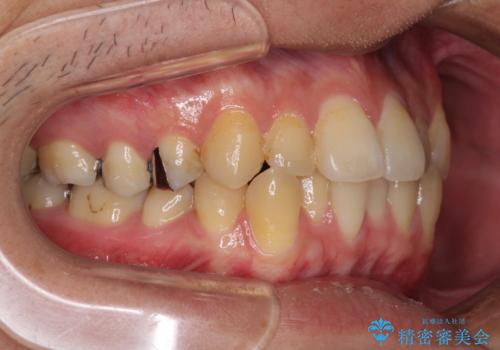

インビザラインによる前歯のクロスバイト改善におけるリスクとして、前歯歯髄充血・歯髄壊死が挙げられます。

ワイヤー矯正を併用する目的として、短期間でデコボコやクロスバイトを改善する他に、歯髄充血リスクを低減させるというものがあります。